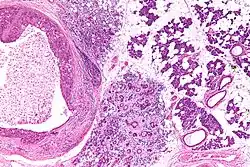

| Low magnification micrograph of a salivary duct carcinoma with characteristic comedonecrosis (left of image) adjacent to normal parotid gland (right of image). H&E stain. | |

Salivary duct carcinoma (SDC) is a rare type of aggressive cancer that arises from the salivary glands.[1] It is predominantly seen in men and, generally, has a poor prognosis.[2] Other high grade carcinomas can mimic SDC. About 40-60% of SDC arise in pleomorphic adenomas.[3] Most, if not all, SDCs express androgen receptor by immunohistochemistry.[4] Therapeutically relevant genetic alterations include ERBB2/Her2 amplification, PIK3CA and/or HRAS mutations.[5][6]

Their histologic appearance is similar to ductal breast carcinoma.